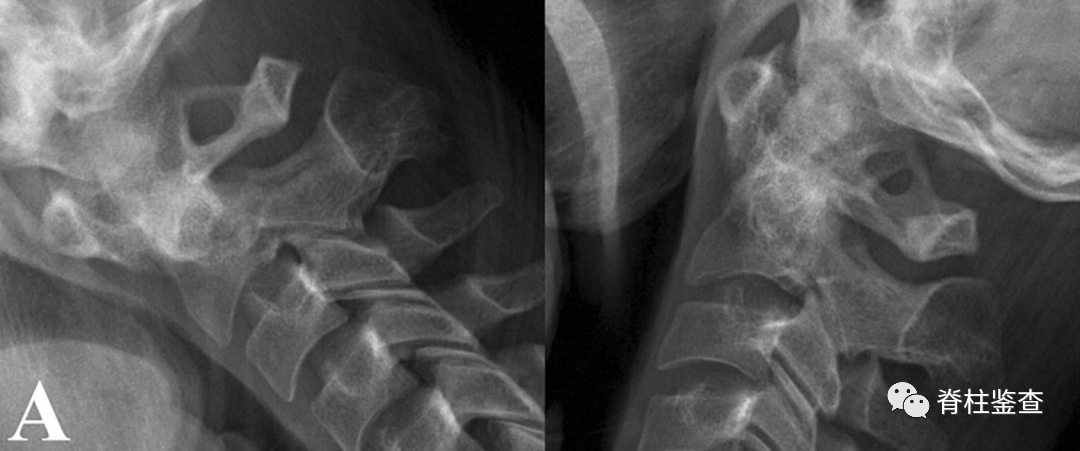

A:术前显示寰枢椎不稳定导致脊髓受压

B:椎弓根狭窄,椎动脉高跨右侧椎弓根螺钉置入风险高

A:术前显示寰枢椎不稳,需要行C1-C2融合

B:椎弓根狭窄,右侧椎动脉高跨